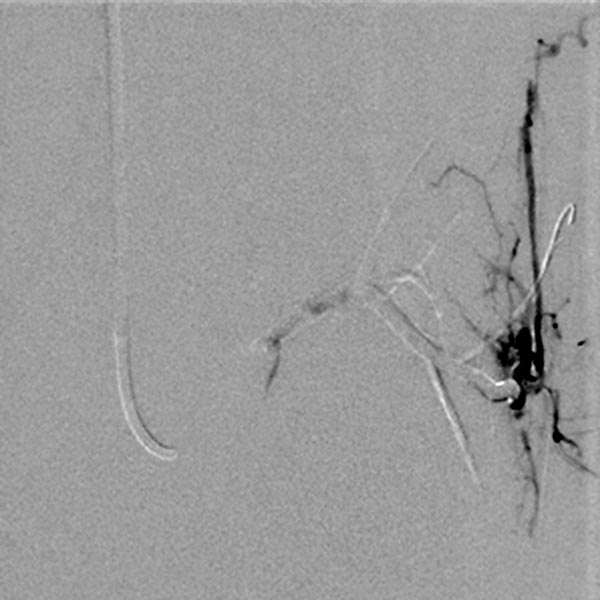

Superselektive digitale Subtraktionsangiographie über einen Mikrokatheter in der Arteria glutea superior in einem distalen Ast. Der Nidus der feinfistulösen arteriovenösen Malformation zeigt so feine Shunts, dass diese anatomisch in der Angiographie kaum aufgelöst werden können.

Während der Embolisation über den Mikrokatheter (nicht abgebildet) in Roadmap-Technik wird das Embolisat (Ethylen-Vinyl-Alkohol-Kopolymer) in den Nidus bis in den venösen Abstrom der AVM vorgedrückt um auch die kleinesten Fisteln zu verschließen („plug & push“-Technik).